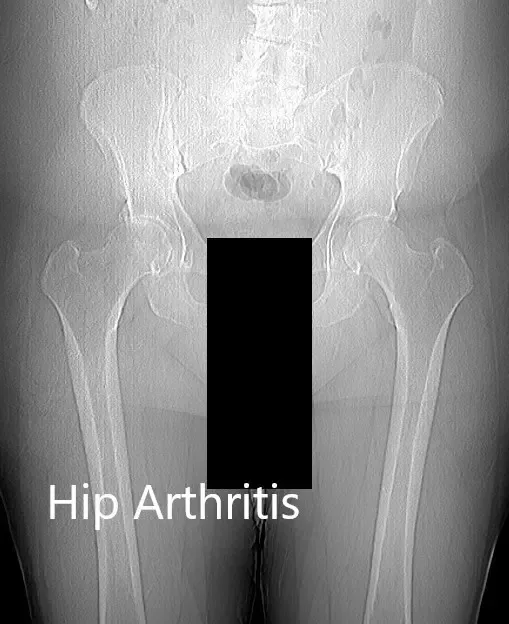

No existía una deformidad fija en el plano coronal, sagital y axial. Los pulsos bilaterales en las extremidades inferiores fueron 2+ y comparables. No había déficit neurológico distal. Las imágenes revelaron osteoartritis severa en ambas caderas con quistes subcondrales, esclerosis y osteófitos.

Radiografía preoperatoria de la pelvis del paciente con ambas caderas.